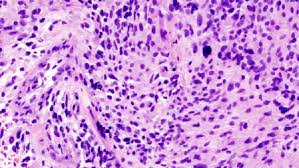

By jillian mock sep 18, 2020 11:45 am (credit: Interestingly, the tumor development was found on the side of the head in which the cellphone was most used. This is ominous because as in smoking and cancer induction, a certain time span is required before cancer sets in the body and is recognised as such by medical and scientific bodies. Nearly 78,000 new cases of primary brain tumors are expected to be diagnosed this year. Brain and spinal cord tumors, like other tumors, are caused by changes in the dna inside cells.

Some genes control when our cells grow, divide into new. The standard treatments for brain tumors include surgery, radiation and chemotherapy. (cnn)the incidence rate of aggressive malignant brain tumors in england has more than doubled in recent decades, and a new study questions what could be driving that rise. Unlike cancers that start in other parts of the body, tumors that start in the brain or spinal cord rarely spread to distant organs. Metastatic tumors to the brain affect nearly one in four patients with cancer, or an estimated 150,000 people a year. The cancer cells break away from the primary tumor and travel to the brain, usually through the bloodstream, then commonly go to the part of the brain called the cerebral hemispheres or to the cerebellum. What you need to know. Soft tissue cancers, like those that develop. Some of the cancers that are on the rise are preventable. We found that the incidence rate of all pediatric brain tumors has been on a gradual but steady increase from 1973 to 2008 (p < 0.001). A new study has revealed that 10 years of cellphone use resulted in an average 290% increased risk of brain tumor development. Cancer is on the rise among young people over the past decade, cancers associated with obesity show some of the most troubling increases affecting young adults and adolescents. Dna is the chemical that makes up our genes, which control how our cells function.